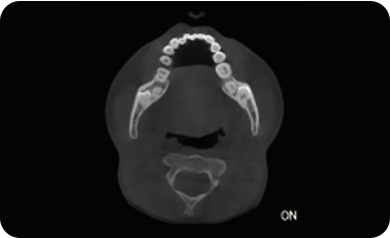

临床样片